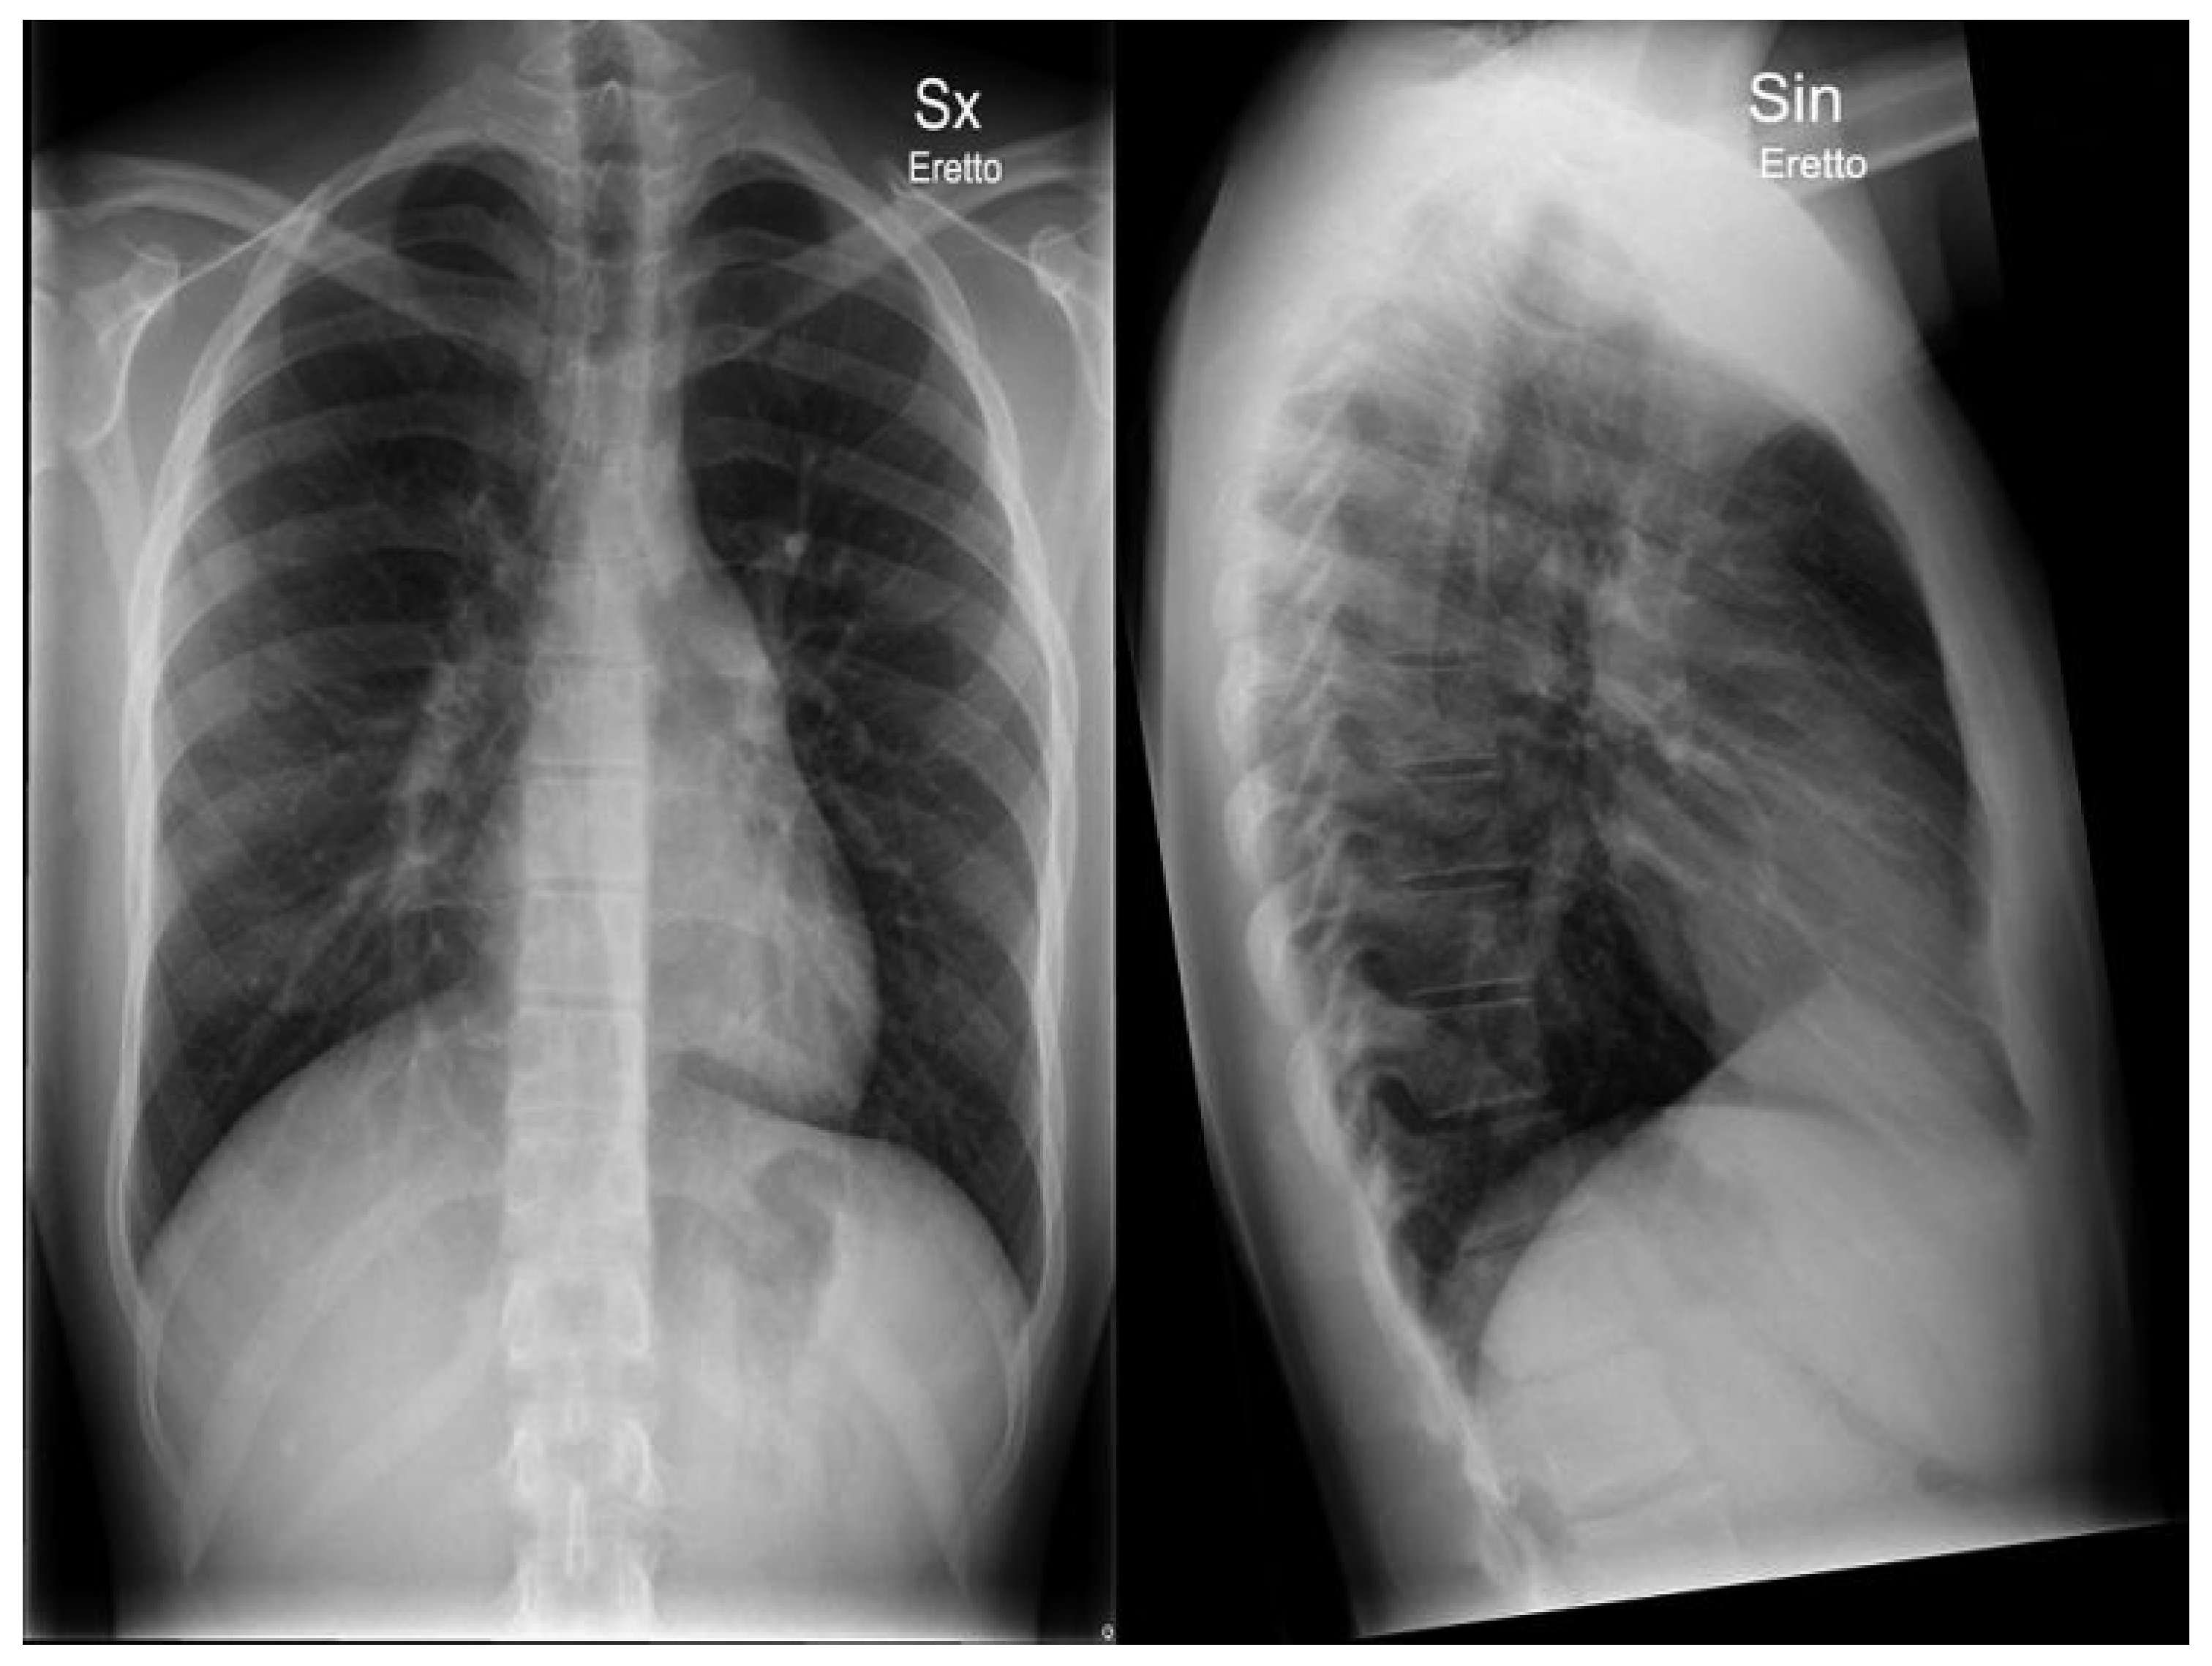

Typical Signs of Secundum Atrial Septal Defect in a Young Man

Case report